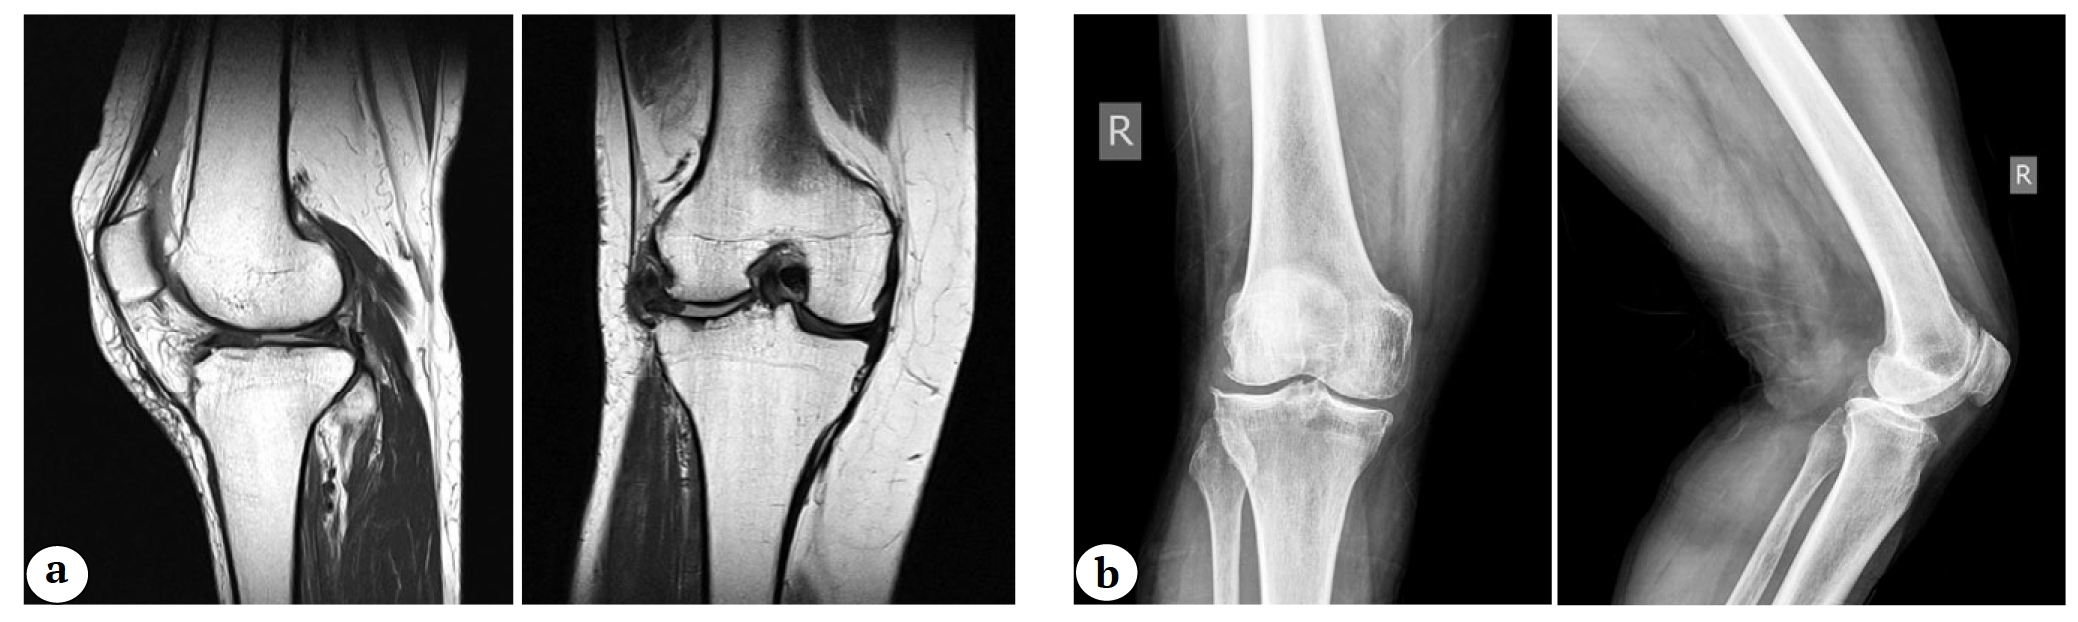

- изолированный идиопатический гонартроз с полнослойной потерей хряща в латеральном отделе сустава, подтвержденный с помощью МРТ и рентгенограмм (в т.ч. с нагрузкой) (рис. 3);

Рис. 3. Признаки локального поражения суставного хряща латерального отдела коленного сустава: а — магнитно-резонансная томограмма латерального отдела коленного сустава; b — рентгенограммы коленного сустава в прямой и боковой проекциях

Fig. 3. Signs of local cartilage damage in the lateral knee compartment: a — MRI images; b — X-rays images in anterior-posterior and lateral projections